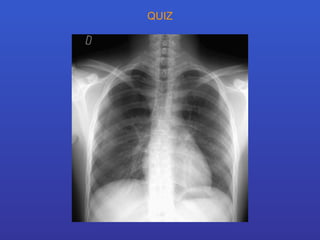

QUIZ